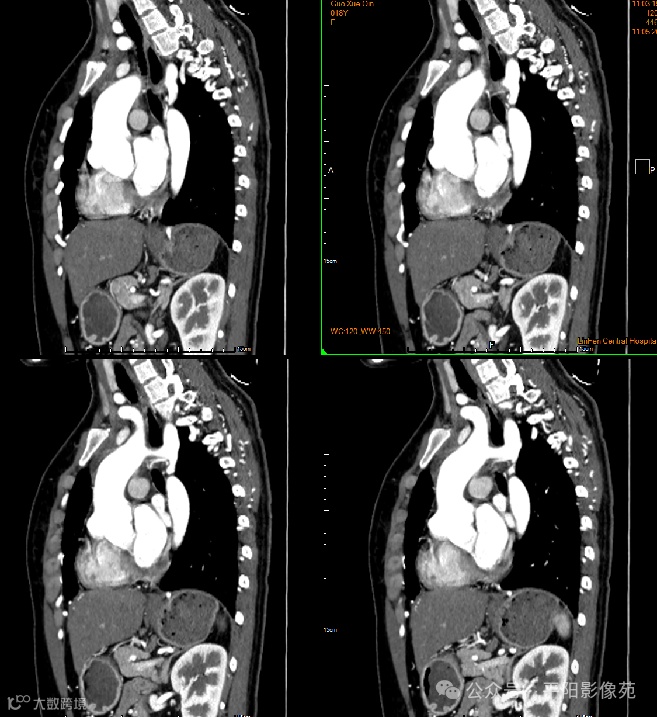

影像检查